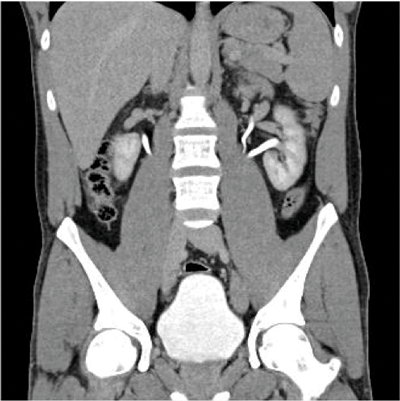

Figure 1b: CT showing enhancing midline isthmus connecting both kidneys.

A horseshoe kidney (Figure 1) is a congenital anomaly in which kidneys are fused by the isthmus at the lower poles. In 90% of cases this is a midline, or symmetrical fusion, but lateral fusion is also a variant. The axis of each renal pelvis remains vertical or in the obliquely lateral plane, and the calyces point posteriorly. The horseshoe kidney lies ectopically with the isthmus located adjacent to the L3 to L4 level. This is due to the inferior mesenteric artery preventing further ascent as it crosses the isthmus. Approximately one third of horseshoe kidneys have a single renal artery to each renal pelvis, whereas the remainder have a variable blood supply [1].

On the plain abdomen film the lower poles of the kidneys are seen medial to the upper poles, in contrast with normal renal anatomy where lower poles are lateral. Ultrasound may reveal the isthmus lying anterior to the spine and contiguous with the lower poles of both kidneys. However due to the positioning of bowel gas centrally, the isthmus may not be clearly viewed and appearances may be of a curved configuration to the kidneys with poorly defined lower poles. In the longitudinal plane the kidneys may appear as an inverted triangular or pyriform shape [3,4]. Contrast enhanced CT will provide the clearest imaging, and helps to define the structural abnormalities of the horseshoe kidney. On CT the following questions can be answered: the degree and site of the fusion, degree of renal malrotation, any associated collecting system abnormalities, and any renal parenchymal changes. CT enables differentiation between normal and fibrous parenchyma within the isthmus, which is almost always functioning tissue.

CT angiography is useful in evaluating arterial anatomy as horseshoe kidneys often have variant arterial supply, including multiple renal arteries, arteries arising from aorta or common, internal or external iliac, or inferior mesenteric arteries [5]. Nuclear medicine imaging can demonstrate fusion with functional parenchymal tissue, and can detect regional loss of function due to obstruction and inflammation [3].